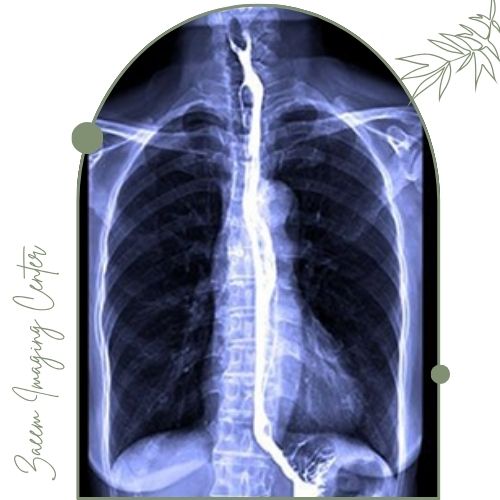

رادیوگرافی الایمنت ویو برای ارزیابی دقیق وضعیت ستون فقرات، زانو و استخوانها در حالت ایستاده